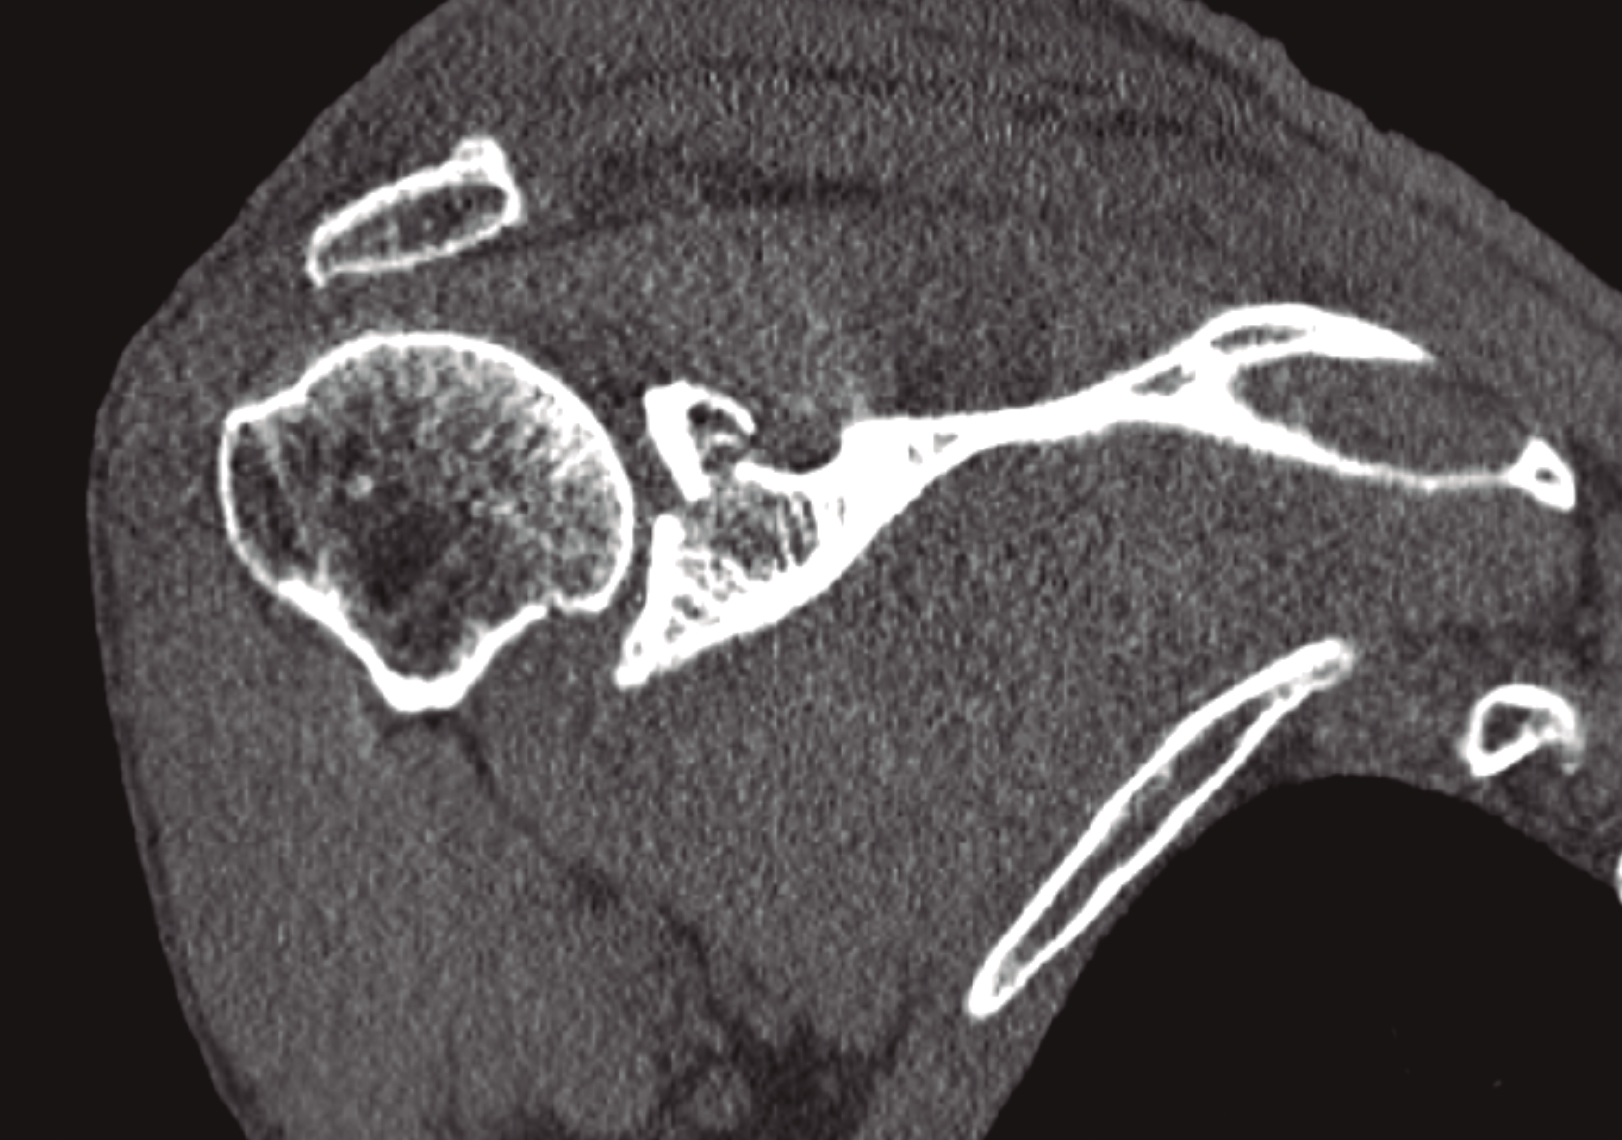

Completamos el estudio con una tomografía computarizada (TC) que nos informa de fractura conminuta del acromion con leve desplazamiento y fractura de la cavidad glenoidea con trazo transverso supraglenoideo que incluye la apófisis coracoides, con desplazamiento de los fragmentos mayor de 1 cm y que supone un escalón articular de 3,5 mm (Figura 2).

Figura 2. Obsérvese el importante desplazamiento que presenta la fractura del margen superior de la glena.

Como se ha comentado, dicho patrón supone una lesión del complejo suspensorio del hombro a doble nivel, ya que presenta fractura del acromion y de la fosa glenoidea con desplazamiento significativo. Por tanto, además del problema de la congruencia articular, existe un problema biomecánico por la disrupción del complejo suspensorio superior del hombro (CSSH). Ante esta lesión, se indica la necesidad de reducción quirúrgica y estabilización de la fractura articular de la glenoides y del acromion.